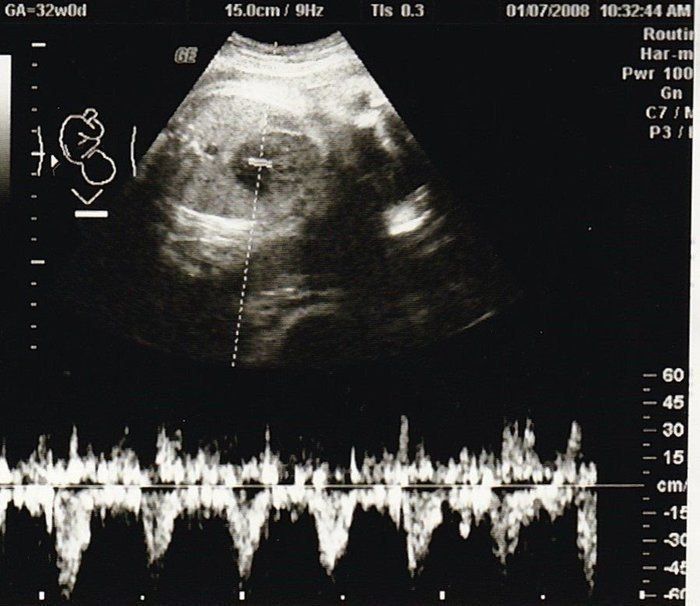

セイコさんの妊娠32週目のエコー写真 少し血圧が高く、浮腫も出てしまう

おなかの中はどうなっていくの? エコー写真で振り返る、高齢ママのはじめての妊娠生活

今日で東京のお医者様の健診は最後です。最後の最後で、血圧がやや高めなことと、少し浮腫みが出てしまって心配をかけてしまいました。娘は順調で、立派な太ももの骨を見せてもらいました。